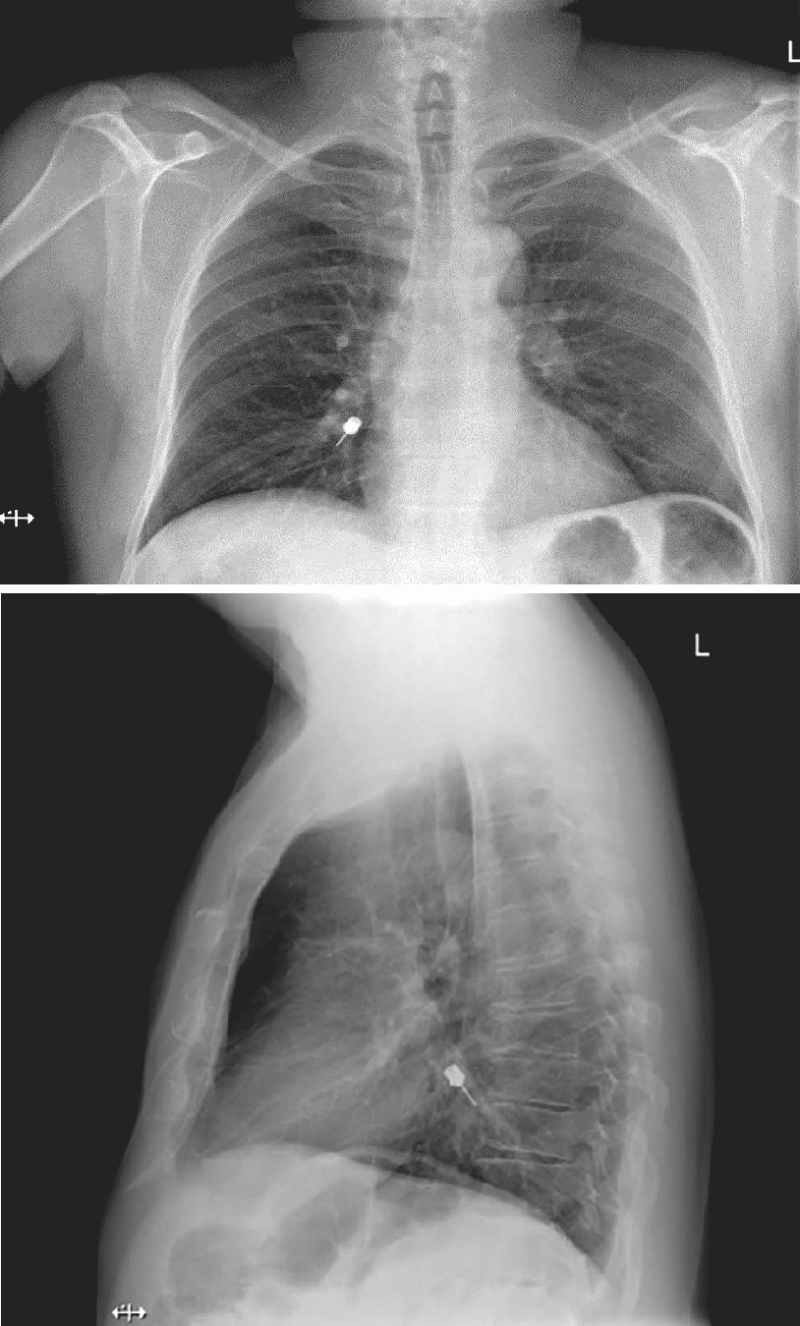

Figure 1 from Foreign Body Aspiration in Dentistry Semantic Scholar Define Aspiration Dentistry The key to managing aspiration is of course prevention, 1 but in the emergent situation, the patient should be quickly put into. An aspirating syringe is used to inject anesthetic from a carpule loaded in the syringe barrel. Dentists and other staff in health centers and free clinics should be aware of ingestion or aspiration risks that exist during dental. Define Aspiration Dentistry.

Figure 2 from Management of foreign body aspiration or ingestion in dentistry. Semantic Scholar Define Aspiration Dentistry The key to managing aspiration is of course prevention, 1 but in the emergent situation, the patient should be quickly put into. Aspirations associated with dental procedures are typically composed of inorganic materials. Dental treatments can be associated with. Local anesthesia is essential for pain management in dentistry. A review of dental aspirations found. An aspirating syringe is used to. Define Aspiration Dentistry.

Aspiration of an Instrument During Dental Treatment (04.06.2021) Define Aspiration Dentistry In patient care, the term aspiration is often used to describe the inflow of material from the oral cavity or upper gastrointestinal tract into the lungs. A review of dental aspirations found. The key to managing aspiration is of course prevention, 1 but in the emergent situation, the patient should be quickly put into. The aspiration of objects and foreign. Define Aspiration Dentistry.